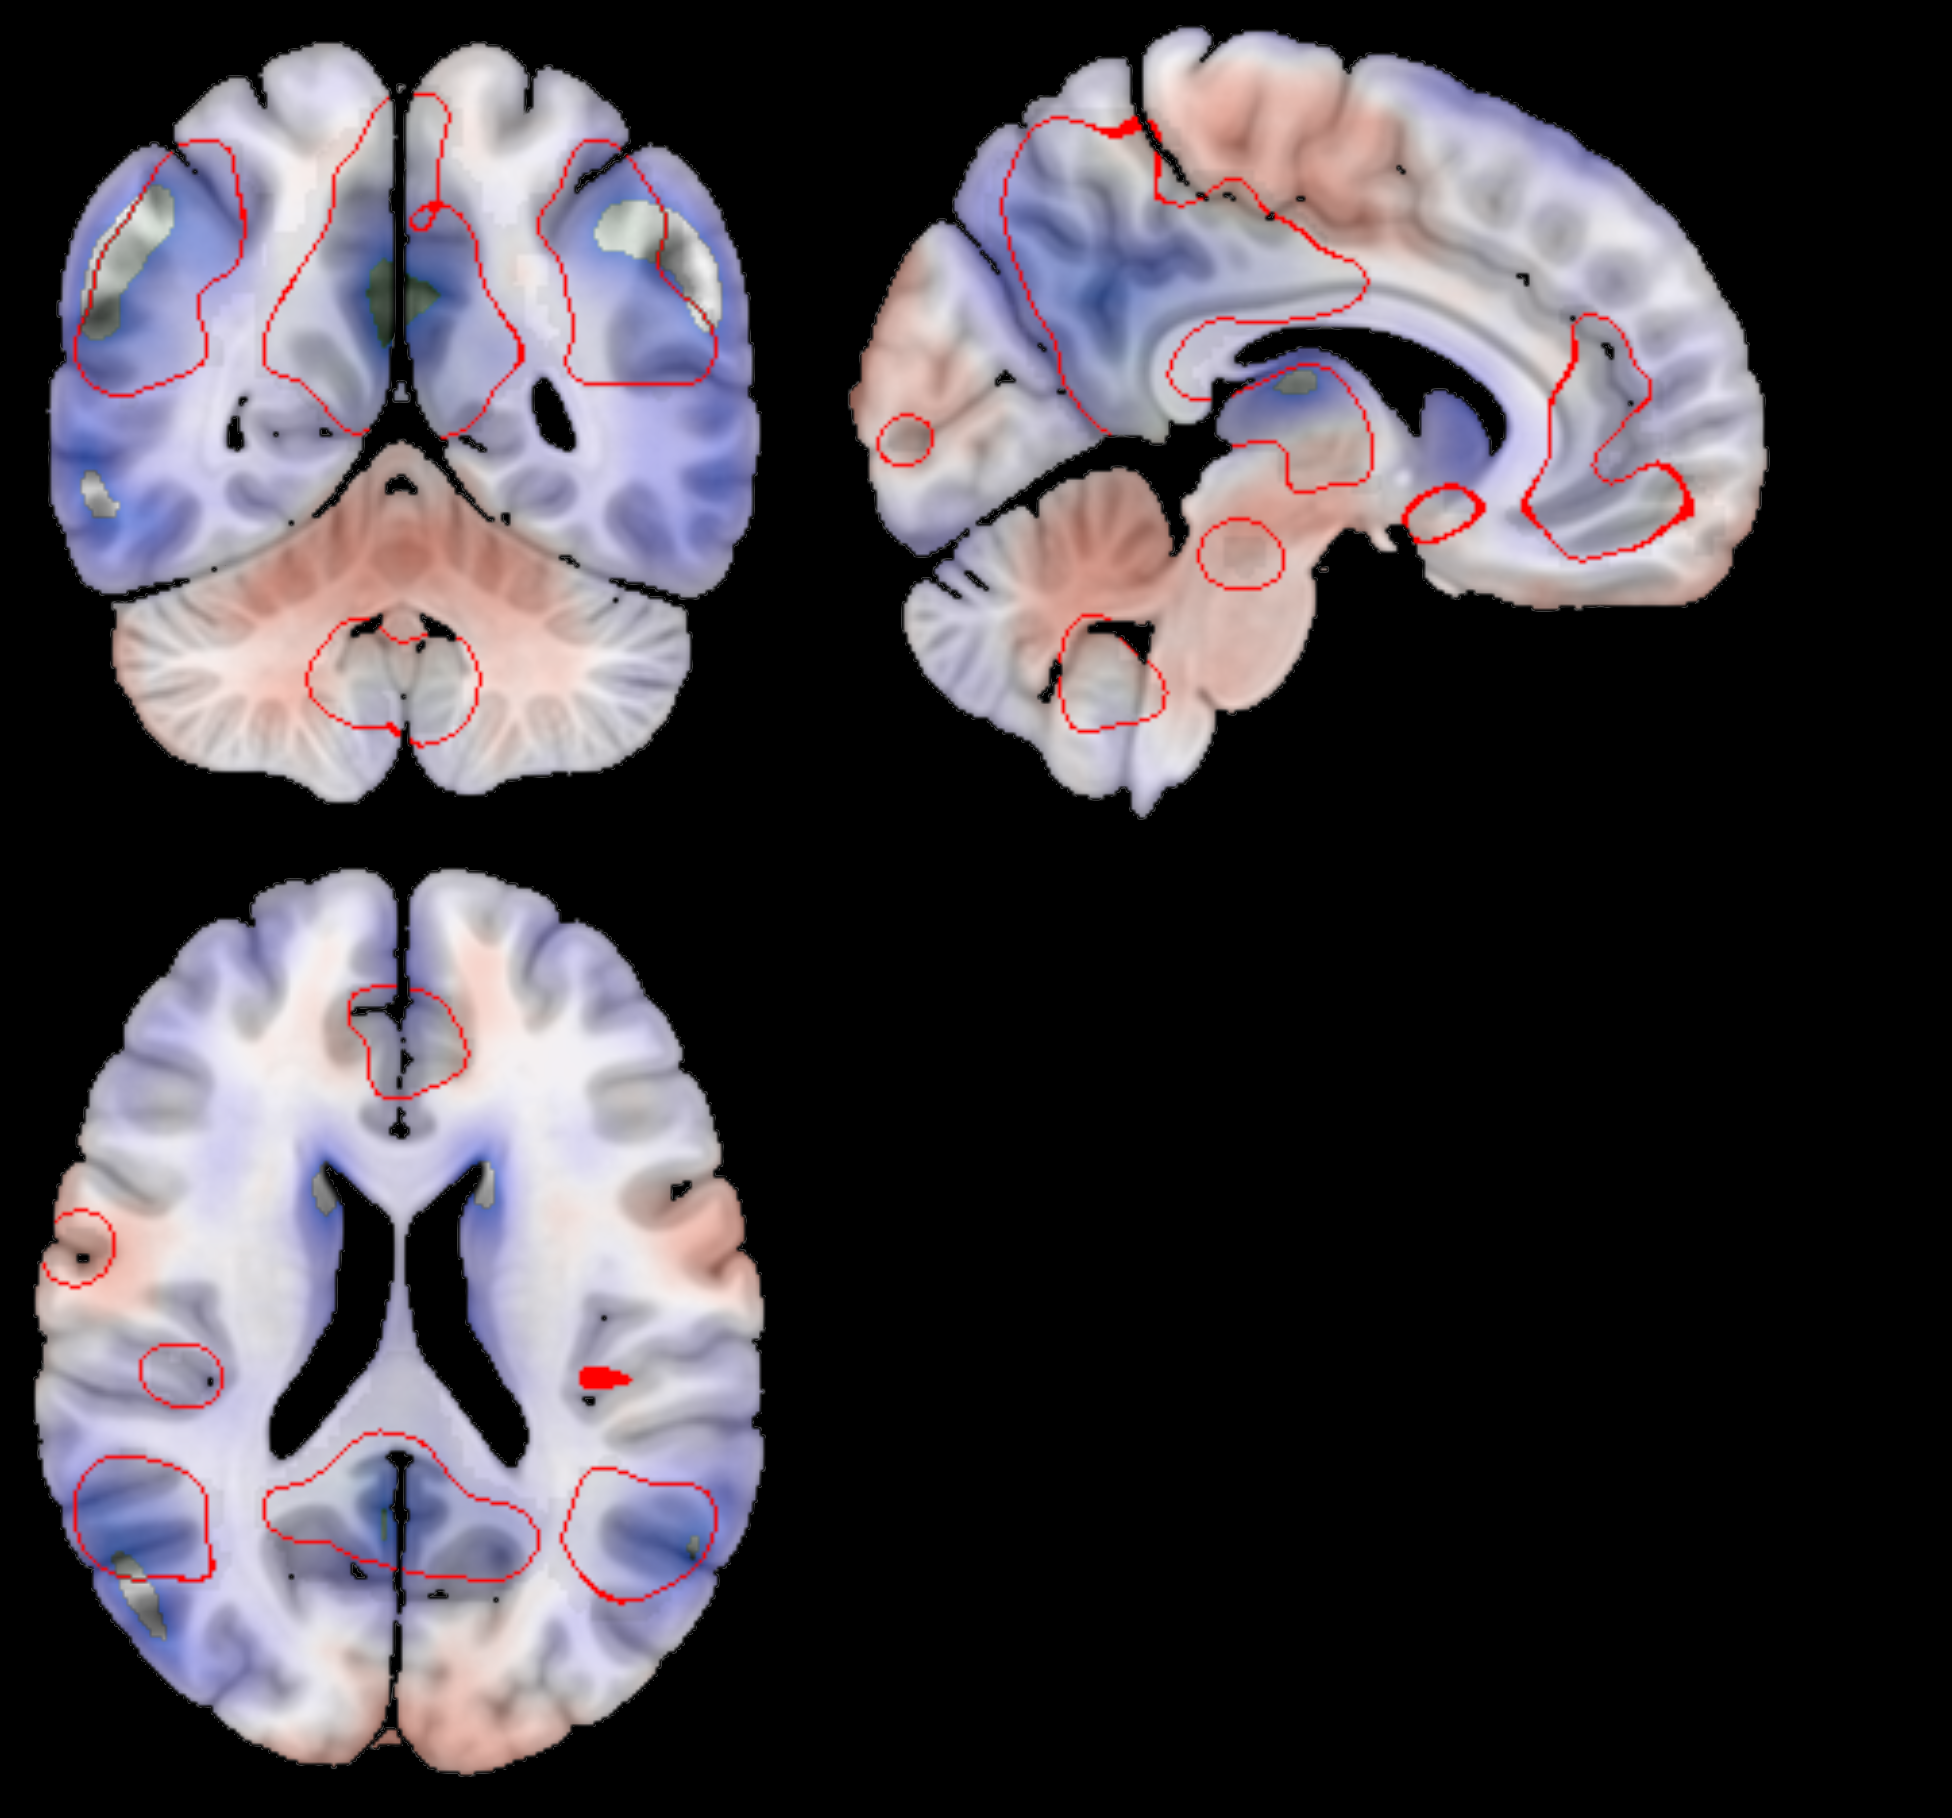

To further investigate the biological relevance of , we generated average latent representations corresponding to fixed values of this variable within its observed range (see Fig. 5). These representations were decoded into brain space, and a voxel-wise GLM was applied to identify structural changes. The resulting statistical map (Fig. 7) highlights regions most affected by neurodegeneration. Decreased metabolism (in blue) was predominantly observed in the prefrontal and medial temporal cortices, as well as in parts of the occipital lobe. In particular, Fig. 7(d) reveals a well-defined decline in metabolic activity in the hippocampal region. In contrast, increased metabolism (in red) was found in the motor cortex and various subcortical structures, as found in literature Mosconi (2005); Minoshima et al. (1997); Robert B. Daroff (2016).

Additional insights are provided in Figs. 7(b), 7(c), 7(e), and 7(f), which show the voxel-wise GLM coefficients overlaid on key RSN s. These include the DMN and the left and right Fronto-Parietal Networks (FPNs). Both the DMN and FPN s demonstrated significant reductions in metabolic activity, whereas the Sensorimotor Network exhibited either no significant changes or slight increases in metabolism.

The generative nature of the VAE allowed us to map these dementia patterns back to brain space, providing an interpretable framework for visualizing the patterns learned by the model to distinguish between AD subjects and normal controls. By performing a GLM on reconstructions of subjects with different values of the first latent variable, we were able to visualize the variations due to dementia in the brain space (Fig. 7). We found that the patterns learned by the model correspond to well-known regions affected by the disease. A marked reduction in glucose metabolism is observed within the DMN —a well-established hallmark of AD Greicius et al. (2004); Buckner et al. (2008), as seen in Fig. 7(b). Similarly, Figs. 7(c) and 7(e) show that the CEN, which encompasses both FPN s, also shows reduced metabolic activity, in line with previous literature. The DMN is involved in internally directed cognitive processes such as introspection and memory retrieval, while the CEN supports functions like attention, working memory, and cognitive control Raichle et al. (2001); Seeley et al. (2007). These domains are significantly impaired in AD Sorg et al. (2007); Zhou et al. (2010); Brier et al. (2014), making the observed metabolic patterns both biologically plausible and interpretable.

In contrast, the Sensorimotor Network —typically preserved in AD —shows either a slight increase or no significant change in metabolic activity. These patterns are clearly localized by our model mainly to the precentral and postcentral gyri, areas responsible for voluntary motor control and somatosensory processing Mosconi (2005); Sperling et al. (2010). We observe a similar behavior in the central occipital cortex, which is also known to be unaffected by AD Scahill et al. (2002).